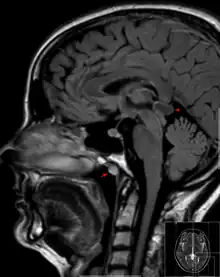

| Tornwaldt cyst imaged on sagittal MRI (FLAIR). The cyst appears hyperintense in the midline of the nasopharynx (arrow). In this case there is also a cyst of the pinealis gland (arrowhead) showing a signal intensity slightly higher than the CSF. | |

A Tornwaldt cyst also spelt as Thornwaldt or Thornwald cyst[1] is a benign cyst located in the upper posterior nasopharynx. It was first described by Gustav Ludwig Tornwaldt. It can be seen on computed tomography (CT) or magnetic resonance imaging (MRI) of the head as a well-circumscribed round mass lying in the midline. In most cases, treatment is not necessary. Indications for treatment include symptomatic lesions, large lesions (>1 cm), or lesions adjacent to the eustachian tube orifice.[2]